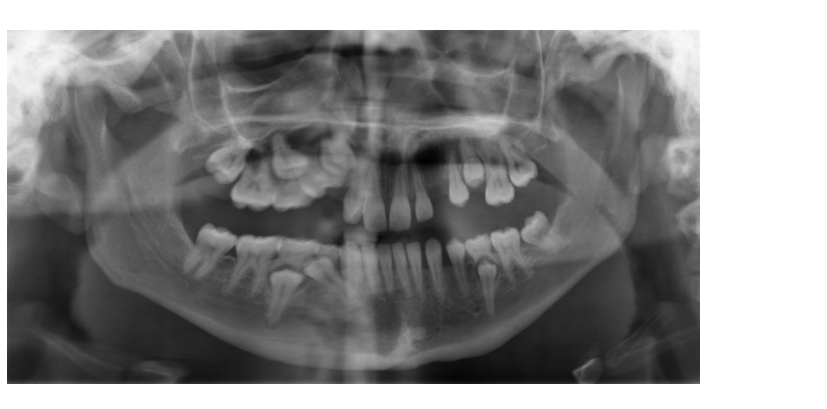

”Rörelse”

Patienten har rört sig under exponeringen vilket ger en vågigt suddig bild som exemplet ovan.